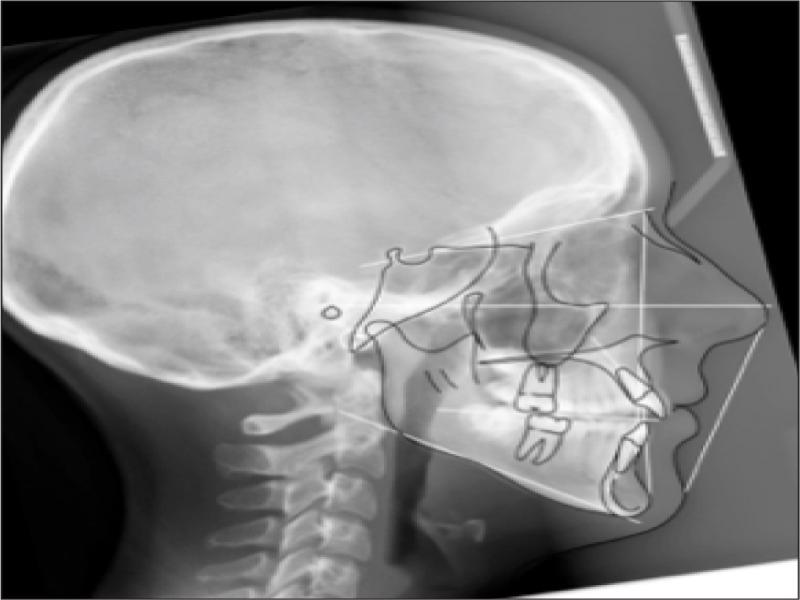

A radiographic examination was unremarkable on the OPG (Figure 2). Cephalometrically (Figure 3, Table I) a Class III skeletal relationship was evident, with a Wits discrepancy of -2.1 mm (due primarily to maxillary retrusion – SNA 72.6°). However, the Class III was camouflaged by the significant vertical disproportion, highlighted by an increased mandibular plane angle (28.6°), reduced facial axis angle (83.2°), reduced Jarabak’s ratio (56.5%), and increased lower anterior facial height (53.4%), all of which indicated a dolichofacial pattern. The maxillary retrusion, combined with a mandibular downward and backward rotation, resulted in a bimaxillary retrusive skeletal relationship (SNB 72.6°). The upper incisors were at an acceptable angulation relative to the palatal plane (112°) and the anteroposterior position relative to Na-Vert. The lower incisors were at an acceptable position relative to APo but were retroclined relative to the mandibular plane (80.7°) according to mesofacial norms.

Pretreatment lateral cephalogram.